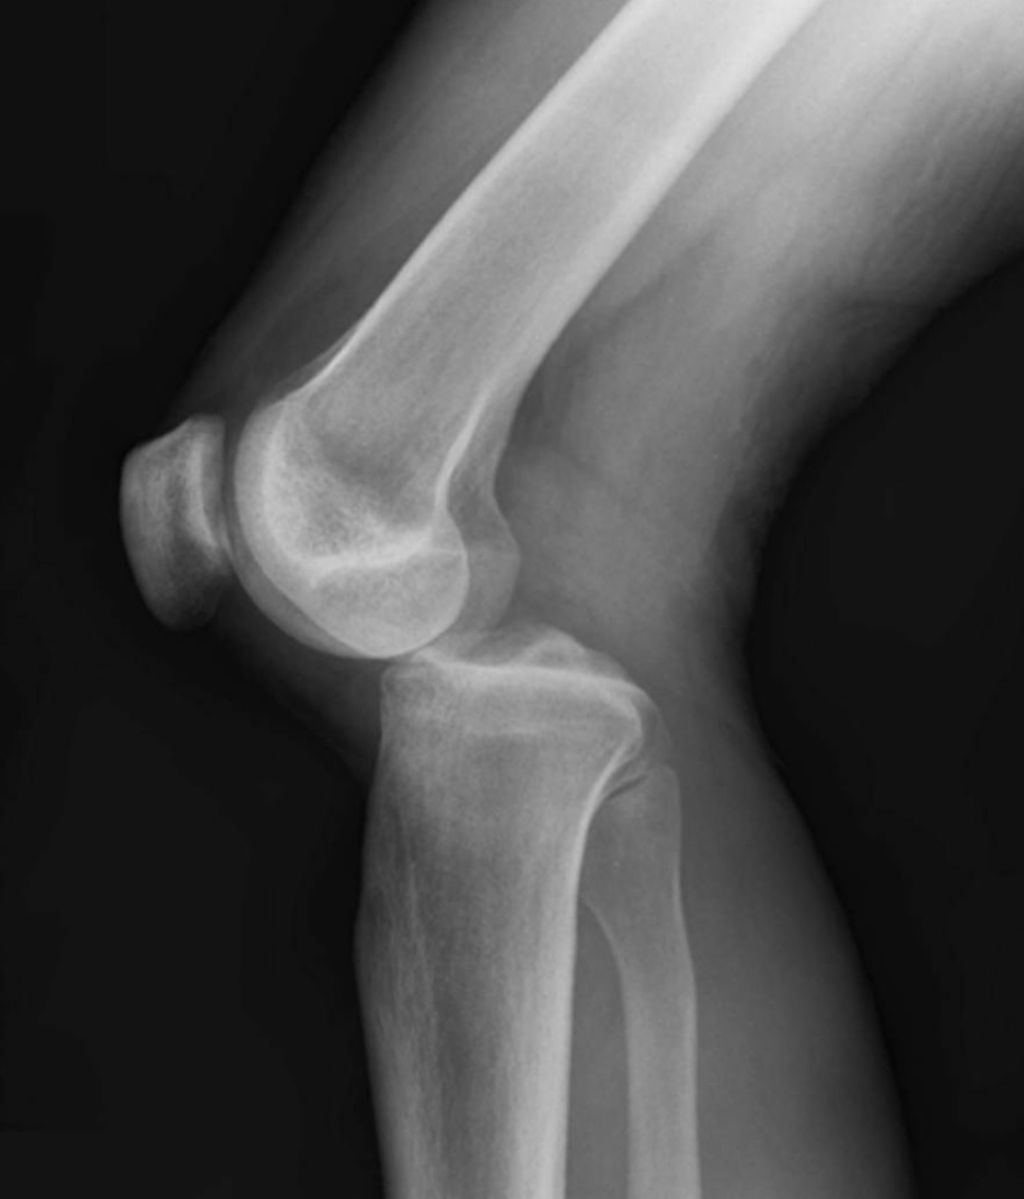

Imaging Studies

After conducting a thorough physical examination, we often turn to imaging studies to gain a deeper understanding of anterior knee pain. These studies provide us with a visual assessment that can reveal structural abnormalities, signs of wear, or other conditions that might not be apparent through physical examination alone.

The most common imaging modalities we utilize include X-rays, magnetic resonance imaging (MRI), and ultrasound. X-rays are excellent for visualizing bone structures and can help us identify fractures or signs of osteoarthritis. MRI scans offer a more detailed view, particularly of soft tissues such as ligaments, tendons, and cartilage. Ultrasound is a real-time imaging technique that can assess the dynamic movement of the knee joint.

Tip: Always consider the patient’s history and physical exam findings when selecting the most appropriate imaging study.

In our quest to accurately diagnose meniscus injuries, we often turn to imaging techniques. These methods provide us with a clear picture of the internal structures of the knee, allowing us to assess the extent of the injury. Magnetic Resonance Imaging (MRI) is the gold standard for visualizing meniscus tears due to its high sensitivity and specificity. However, we also consider other modalities such as ultrasound and X-rays, particularly when MRI is contraindicated or unavailable.

Ultrasound is advantageous for its real-time imaging capabilities, which can be particularly useful in dynamic assessments. X-rays, while not as detailed for soft tissue injuries, can help rule out other conditions such as fractures or osteoarthritis. It’s important to note that while imaging provides valuable information, it should be interpreted in conjunction with clinical findings.